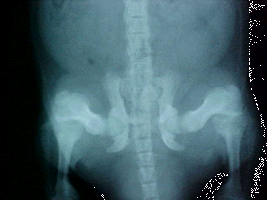

In January 2002 Archie was dragging his hind quarters one morning, took him in to vet for X-rays. He showed 2 fused vertebrae in his spine and hip displaisia - but instead of the ball part being damaged the cup part is. At this appointment, Archie got a time released cortisone shot. I started him on a combination tablet of Glucosamins/Chrondroiton/MSM - name is Move Free Plus MSM.

In February 2002, I started feeding him pinkies [infant rodents] - 5 a day. Other than that the only thing I changed was to give him Liquid Taurine - 1/2 a pump once a day. In October 2002, We re X-rayed Archie's hips and spine. He had regenerated bones! The vertebra fushion was separating also. Archie still gets - 1/2 tablet a day of the Glucosamine combination (Move Free Plus MSM), his pinkies, and Liquid Taurine. I have recently added back into his diet 500mgs Evening Primrose Oil and 50mgs Zinc daily.